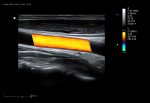

El Doppler Color ViV 20 es un ecógrafo de nueva generación diseñado para ofrecer una experiencia clínica superior con un equilibrio perfecto entre rendimiento, durabilidad y accesibilidad. Su arquitectura avanzada proporciona imágenes claras y precisas, permitiendo diagnósticos confiables en aplicaciones como abdomen, ginecología, vascular, partes blandas y más.

Práctico y fácil de usar, el ViV 20 integra funciones esenciales para el trabajo diario, con herramientas de medición completas, modos Doppler avanzados y optimización automática de imagen. Su diseño resistente garantiza una larga vida útil incluso en entornos de alta demanda, convirtiéndolo en una opción ideal tanto para clínicas pequeñas como para centros médicos con gran flujo de pacientes.

Imágenes clínicas extraordinarias